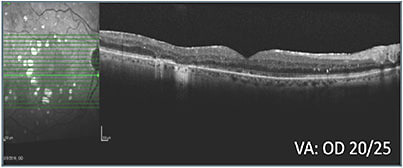

A series of treatments, during the course of which vision ranged from 20/50 to 20/25, failed to resolve the macular edema (B). With vision in the right eye consistently worse than in the left eye and worsening, and the patient experiencing hardship remaining away from home for treatment, an alternative class of therapy was initiated and led to improved retinal anatomy (C, D, & E). Intraocular pressure (IOP) increased to 25 mm Hg and was observed without treatment. When pressure increased to 28 mm Hg, the patient was started on a topical IOP-lowering drop, which lowered the pressure to 19 mm Hg. The right eye has remained fluid free on the alternative class of therapy and a single IOP-lowering agent.